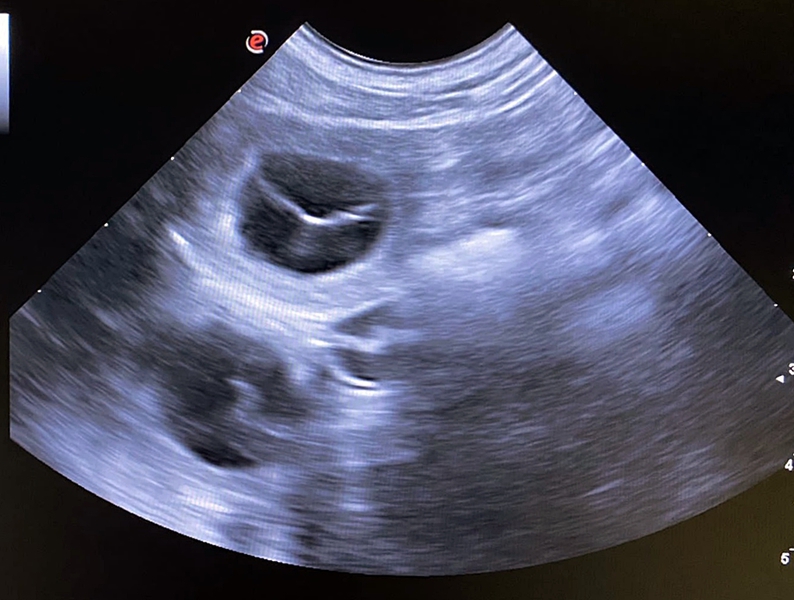

57ter  Trächtigkeitstag......

Es ist ein bisschen unscharf aber wir rätseln ein bisschen und warten ab was unser Königskind Jolie uns schenken wird......

Die Köpfchen wurden auch schon Gemessen....

Gewicht: 14,7 kg